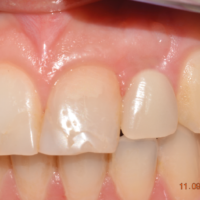

La nostra paziente è una ragazza di ventidue anni, trattata ortodonticamente presso uno studio privato, che si rivolge a noi per sostituire un ponte Maryland, che maschera l’agenesia di un incisivo laterale superiore di sinistra. Da un esame obiettivo iniziale, crediamo che ci siano le condizioni per costruire una corona che rispetti i rapporti dento-dentali con gli elementi contigui (Figg. 1, 2).

- Fig. 1

- Fig. 2